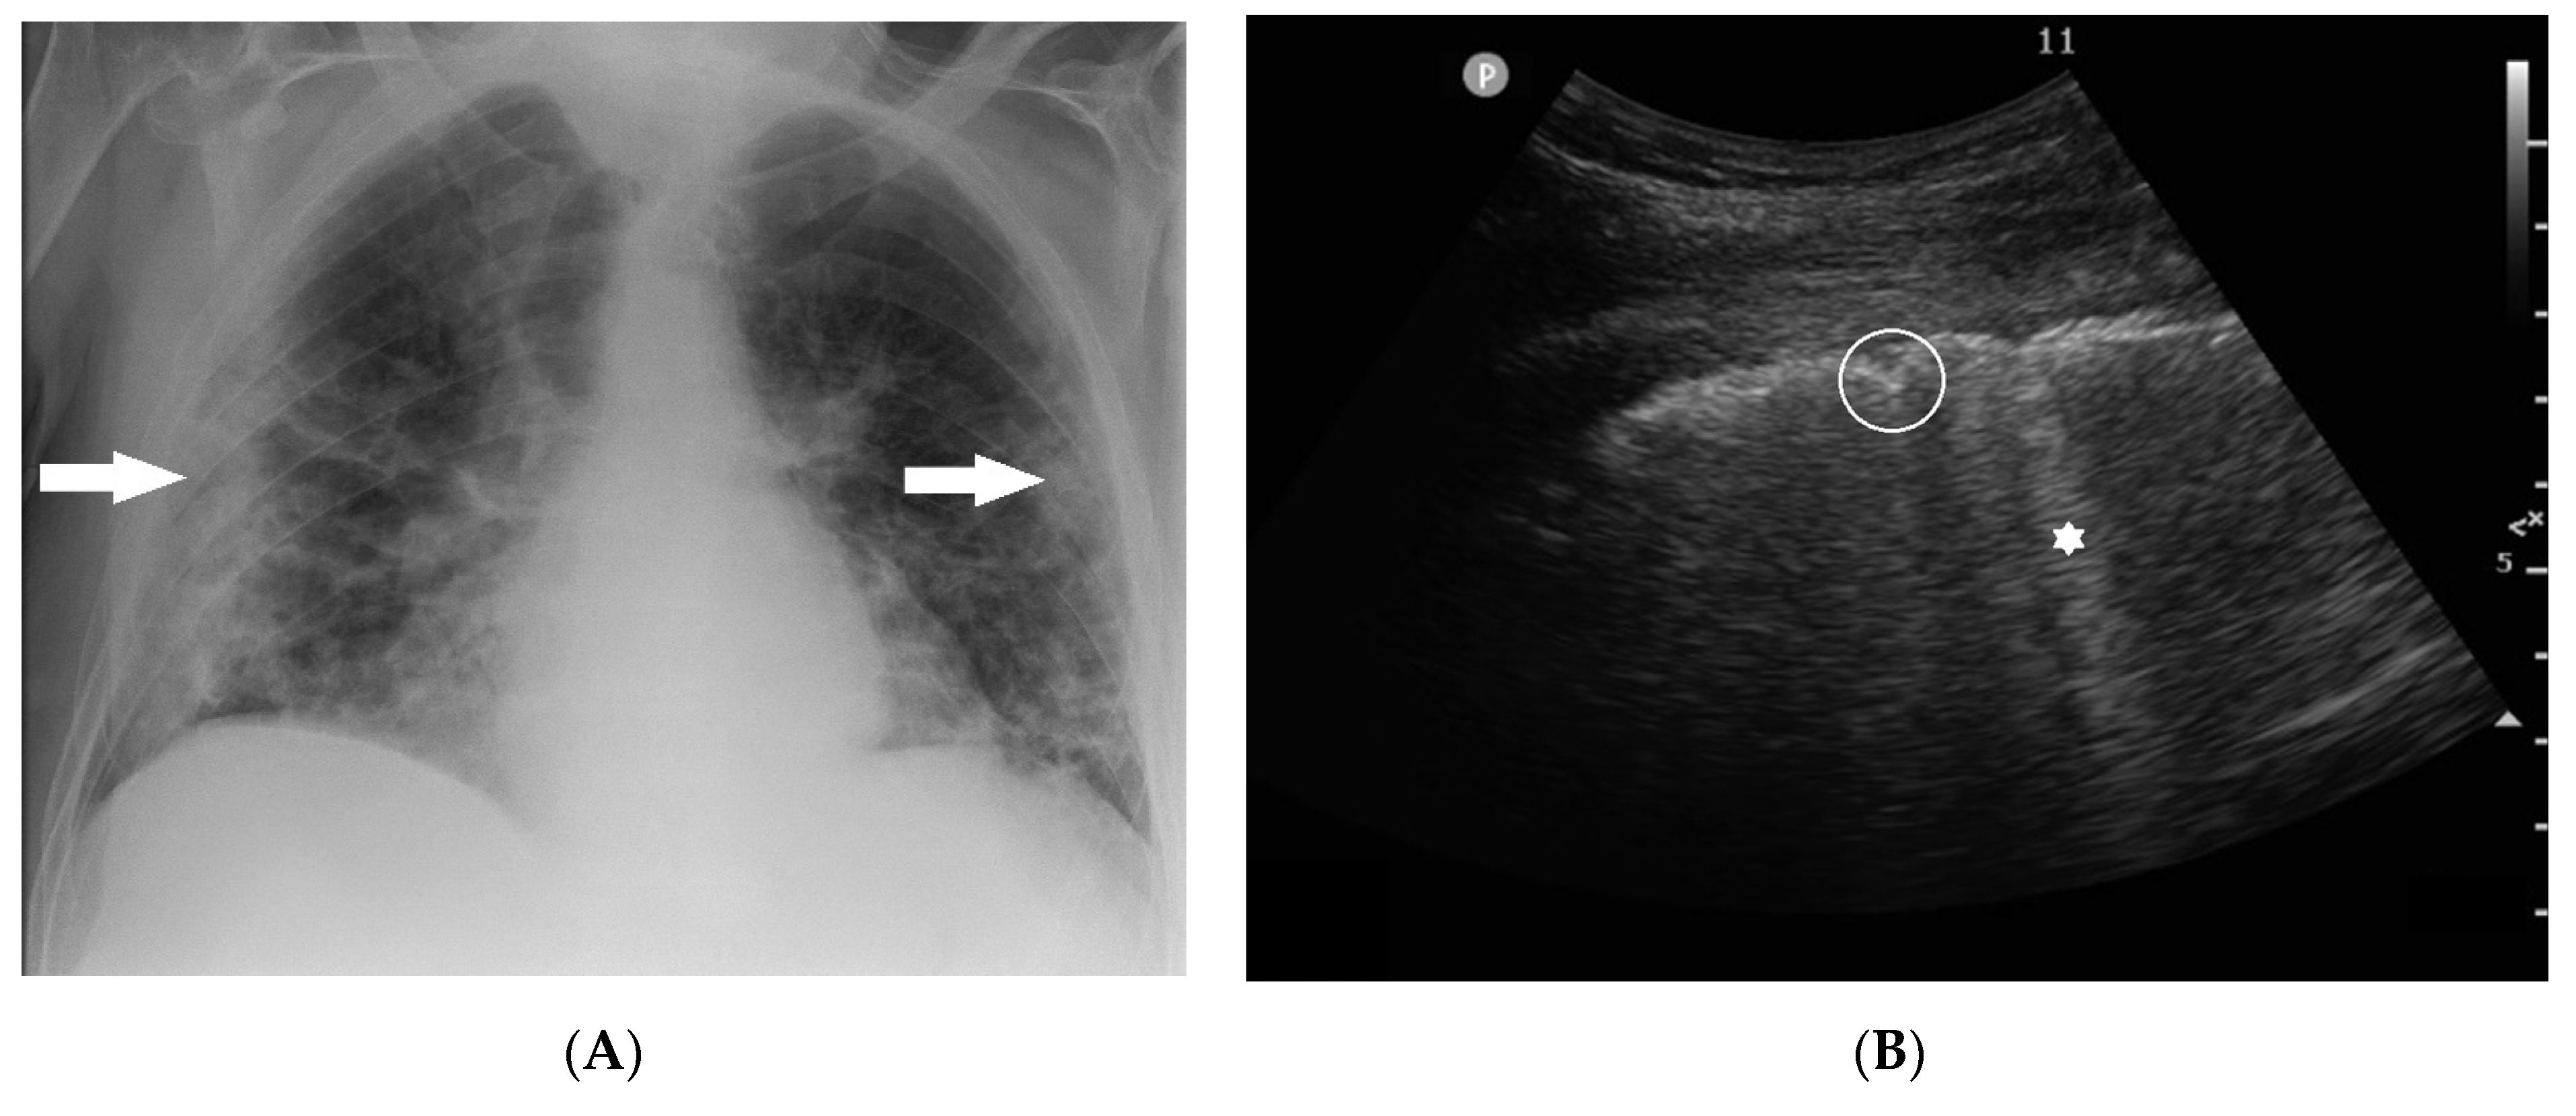

Indulge in the remarkable luxury of our ultrasound vs x-ray-difference between ultrasound and x-ray collection with extensive collections of exquisite images. showcasing the grandeur of music, song, and instrument. perfect for high-end marketing and branding. The ultrasound vs x-ray-difference between ultrasound and x-ray collection maintains consistent quality standards across all images. Suitable for various applications including web design, social media, personal projects, and digital content creation All ultrasound vs x-ray-difference between ultrasound and x-ray images are available in high resolution with professional-grade quality, optimized for both digital and print applications, and include comprehensive metadata for easy organization and usage. Our ultrasound vs x-ray-difference between ultrasound and x-ray gallery offers diverse visual resources to bring your ideas to life. Each image in our ultrasound vs x-ray-difference between ultrasound and x-ray gallery undergoes rigorous quality assessment before inclusion. Advanced search capabilities make finding the perfect ultrasound vs x-ray-difference between ultrasound and x-ray image effortless and efficient. Comprehensive tagging systems facilitate quick discovery of relevant ultrasound vs x-ray-difference between ultrasound and x-ray content. Our ultrasound vs x-ray-difference between ultrasound and x-ray database continuously expands with fresh, relevant content from skilled photographers. Whether for commercial projects or personal use, our ultrasound vs x-ray-difference between ultrasound and x-ray collection delivers consistent excellence.